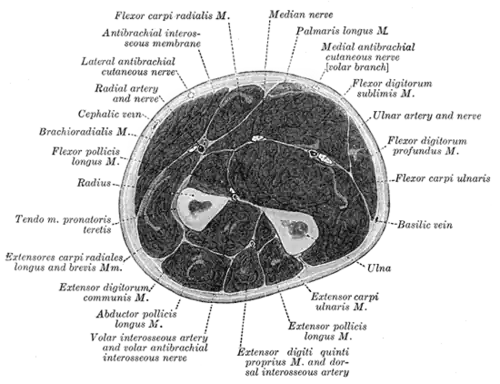

Muskeln und Faszien

Die Muskeln des Unterarmes werden ihrer Lage nach in zwei Gruppen unterteilt: Die Muskeln, die am lose hängenden Arm innen liegen und somit den Arm anbeugen (Flexoren) und die Muskeln, die außen liegen und den Arm strecken (Extensoren). Diese beiden Gruppen bestehen jeweils aus zwei einzelnen Schichten, die von der Körperoberfläche in die Tiefe gehen.

Die Unterarmfaszie (Fascia antebrachii) grenzt die einzelnen Muskelbäuche voneinander ab. Außerdem teilt sie zusammen mit der Bandhaft zwischen den beiden Unterarmknochen (Membrana interossea antebrachii) die Unterarmmuskeln in eine Beuger- und eine Streckerloge. Im Bereich des Handgelenkes ist sie auf der Handrückenseite durch querverlaufende Faserzüge (Retinaculum extensorum) verstärkt. Diese Verstärkung dient als Haltevorrichtung der Streckersehnen. Auf der Handflächenseite verschmilzt die Unterarmfaszie mit den vorderen Faserzügen (Retinaculum flexorum), welche den Karpaltunnel bilden, durch den die Sehnen der Fingerbeugemuskeln verlaufen. Von dem Musculus biceps brachii geht eine zusätzliche Verstärkung der Faszie aus (Lacertus fibrosus).